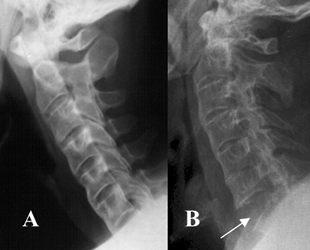

Fig 56 G. Fractura.

A: Rx lateral. Rectificación de la columna y formación de sindesmofitos, por EA.

B: TAC reconstrucción sagital. Antecedente de trauma y no visualización de C7 en la Rx simple. Se identifica aumento del espacio C6-C7, con retropulsión del cuerpo, por lesión traumática.

Fig 56 H. Fractura.

TAC reconstrucción. Fusión de los cuerpos cervicodorsales y aumento de la lordosis. Se identifica fractura de C7, con retropulsión del fragmento inferior.